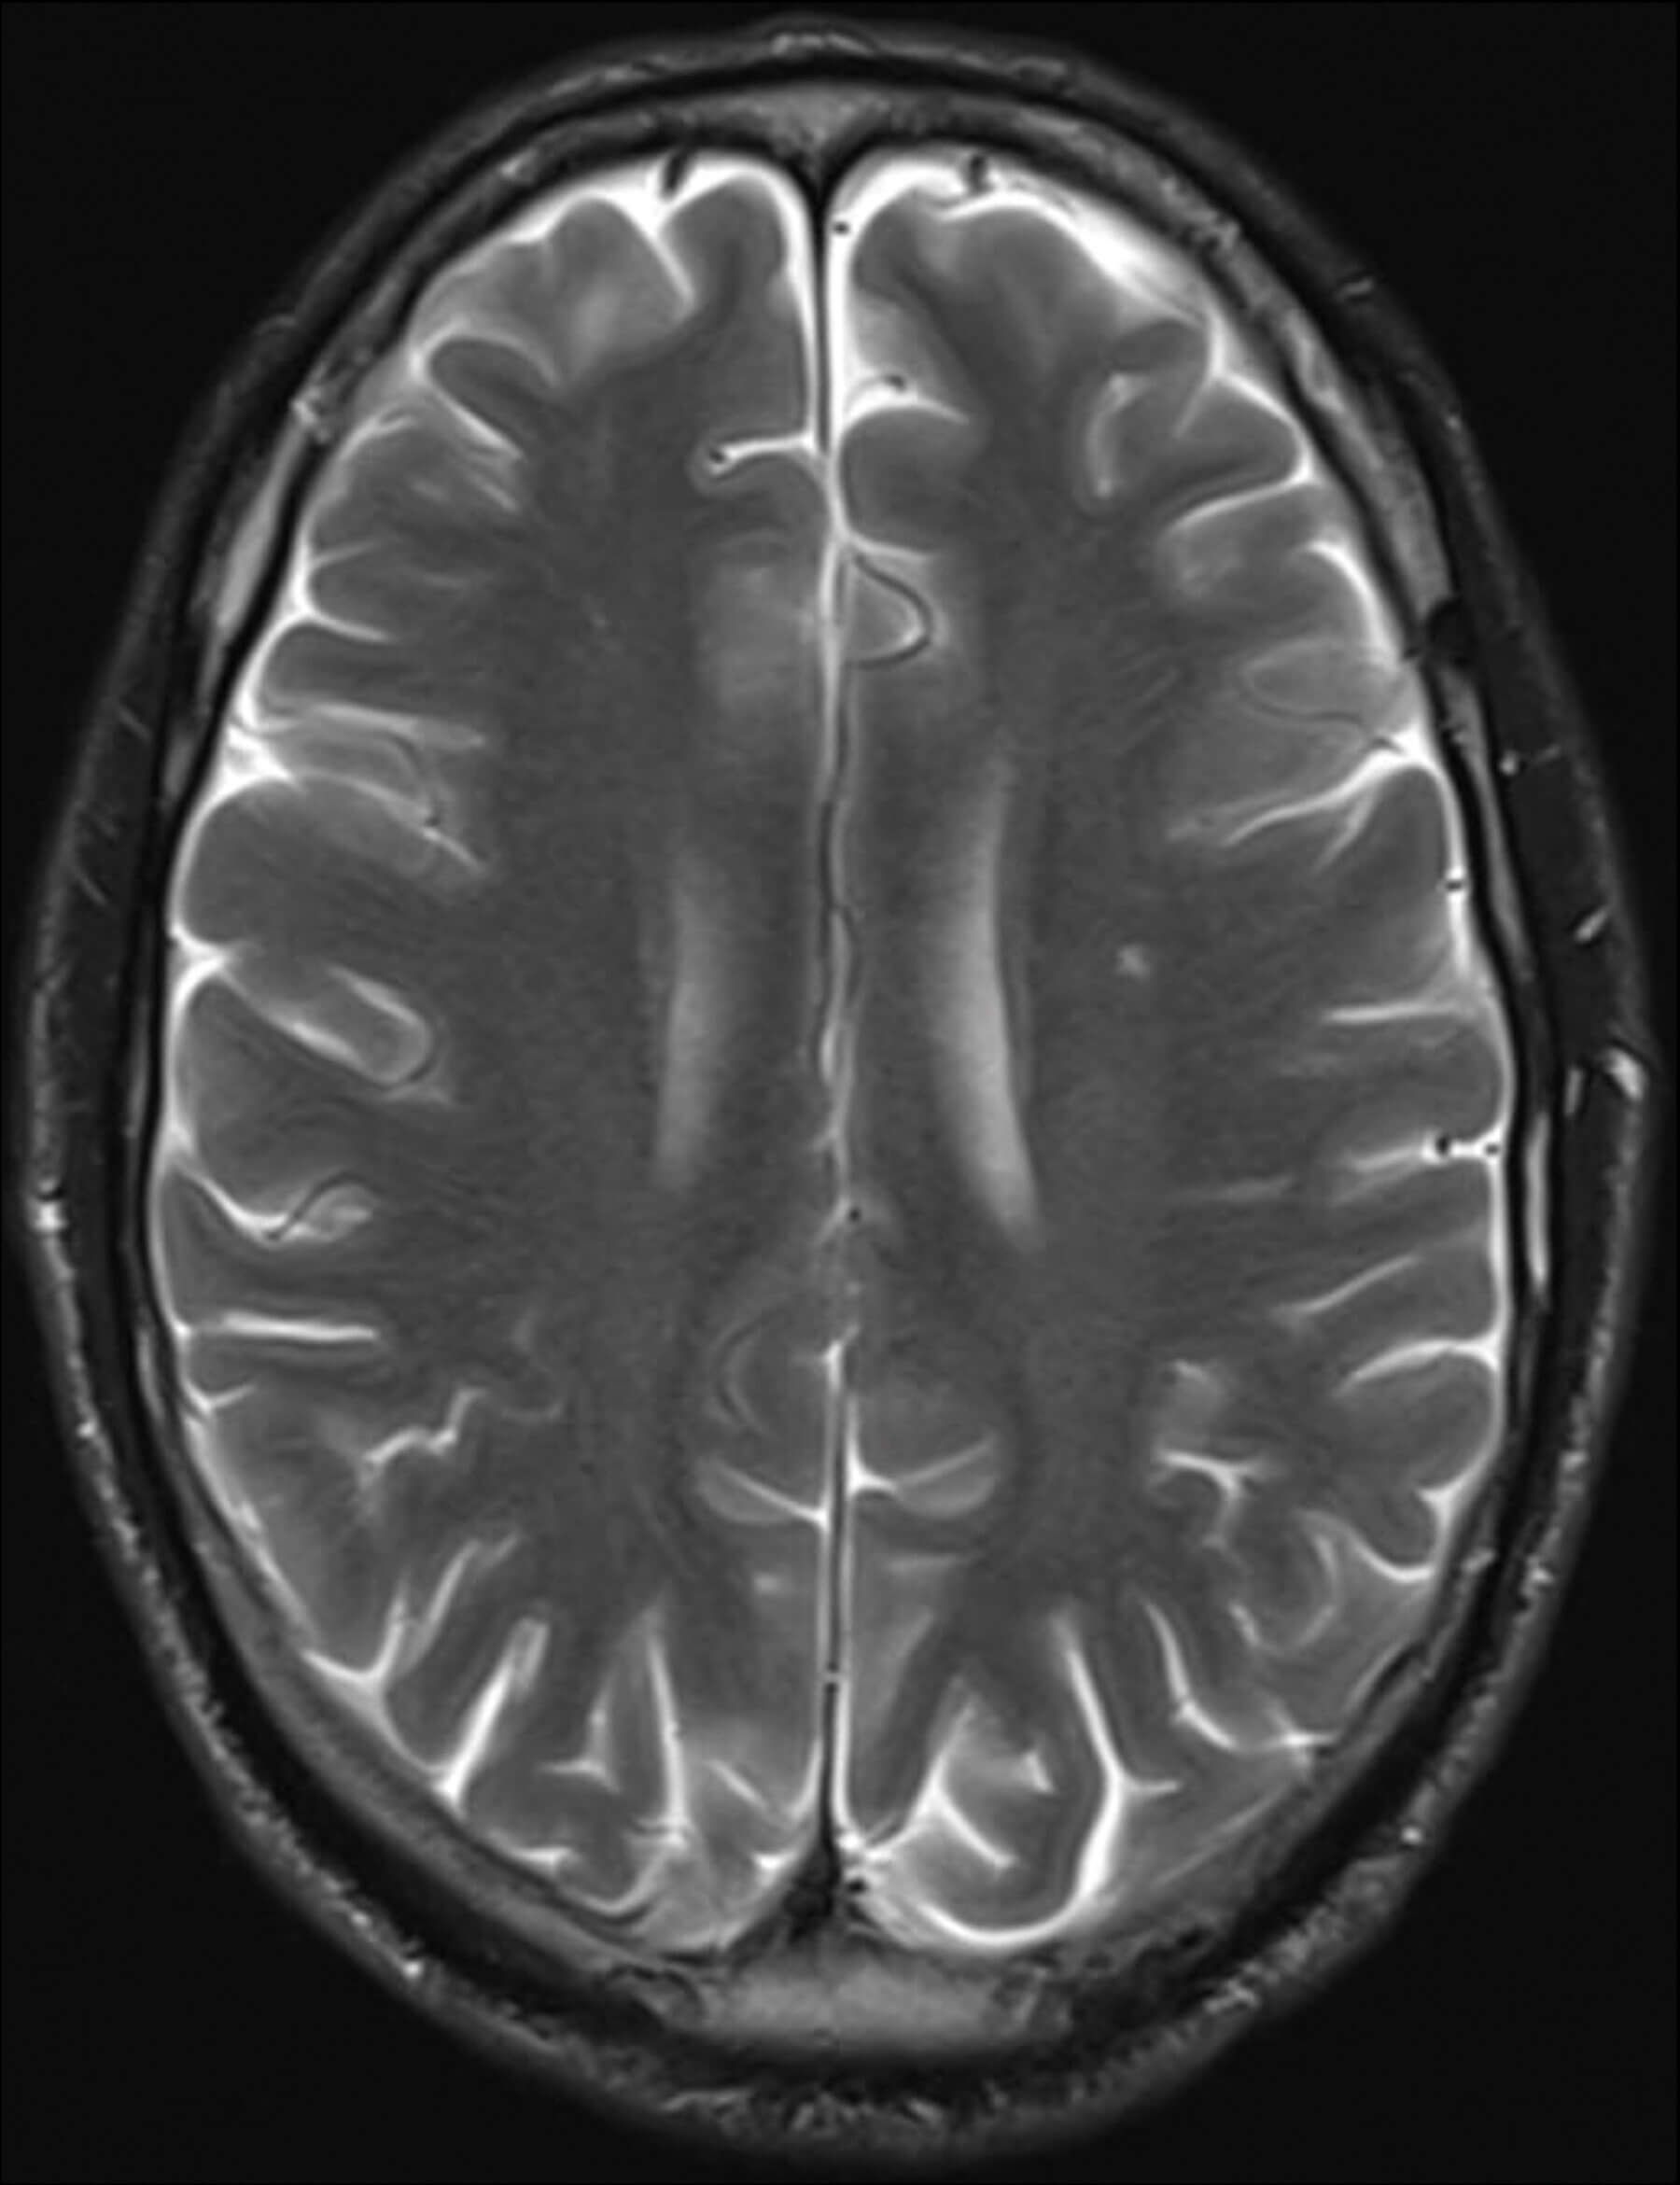

Figure 3: Contrast magnetic resonance imaging. Small nonspecific focus of hyperintensity on T2 and FLAIR sequences within the left centrum semiovale, and mild dural thickening and enhancement overlying the cerebral hemispheres bilaterally.

Contrast magnet resonance imaging (MRI) of head and orbit (Figure 3) showed a non-specific hyperintense focus on T2 and FLAIR sequences in the left centrum semiovale, and meningeal enhancement of both hemispheres. There was no enhancement or abnormality of the optic nerves and no evidence of tertiary syphilis. Cerebrospinal fluid (CSF) obtained by lumbar puncture was positive for TPPA without RPR, likely representing transfer from peripheral circulation and not neurosyphilis.